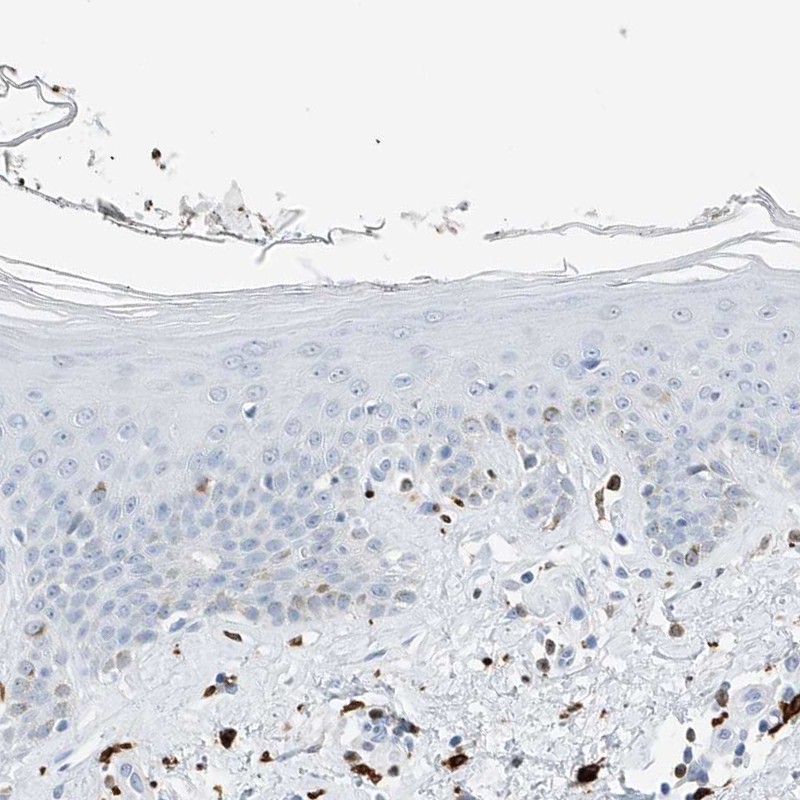

Immunohistochemistry analysis in human spleen and skin tissues using Anti-TBXAS1 antibody. Corresponding TBXAS1 RNA-seq data are presented for the same tissues.